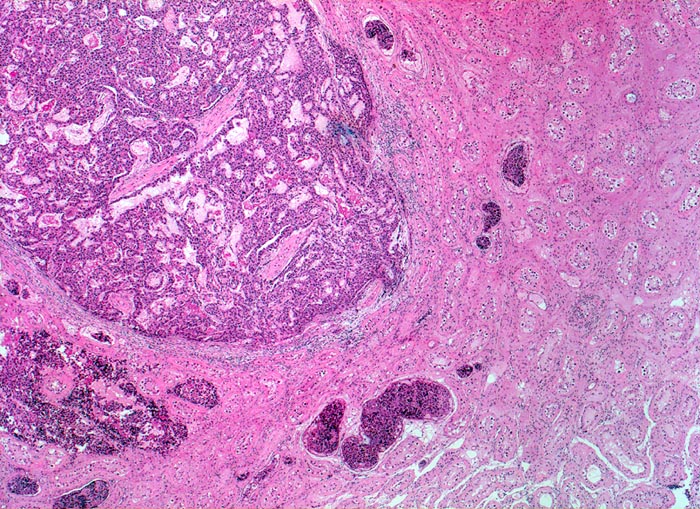

• Polymorphe Tumorzellen bilden miteinander anastomosierende Stränge, solide Zellplatten, glanduläre und kribriforme Strukturen.

• Gefässeinbrüche in peritumoralen Gefässen.

• Tumorinfiltration des peritestikulären Fettgewebes.

Histologisch bilden die Tumorzellen solide Zellplatten, Drüsen oder papilläre Strukturen mit Einblutungen und Nekrosen. Die Tumorzellen sind polygonal, kubisch oder zylindrisch, haben reichlich Zytoplasma und unscharfe Zellgrenzen. Die grossen Kerne haben grob verklumptes Chromatin und enthalten oft mehrere sehr grosse unregelmässige Nukleolen. Gefässeinbrüche und eine testikuläre intratubuläre Neoplasie sind in der Tumorumgebung häufig nachweisbar